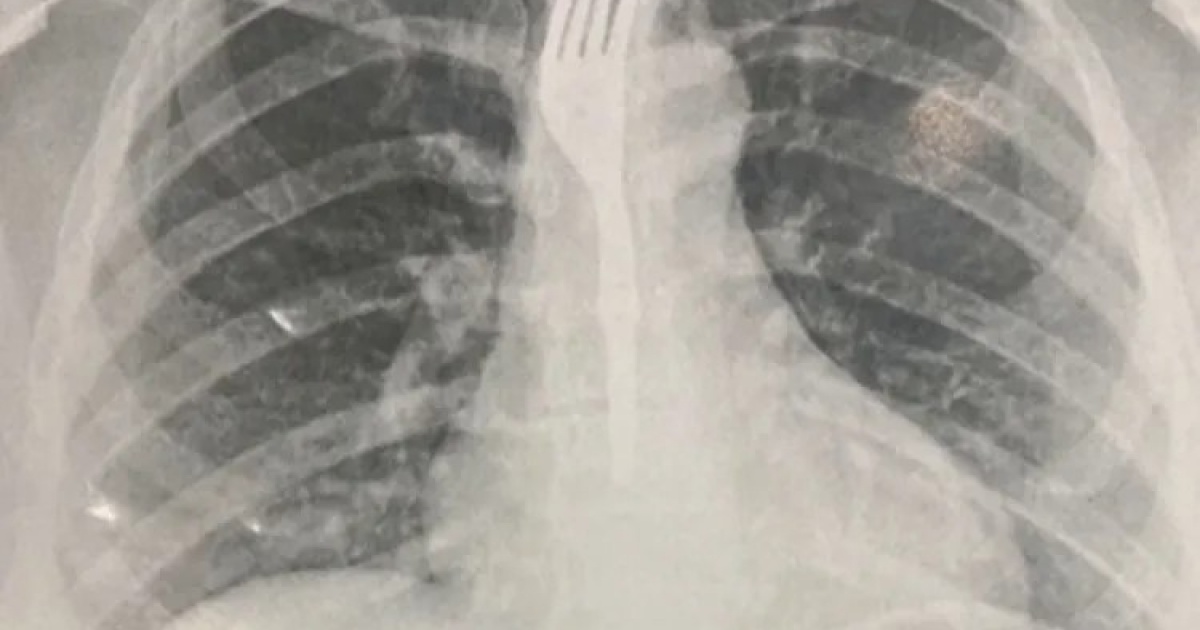

Uma mulher precisou ser transferida para um hospital de Vitória da Conquista, no Sudoeste, após engolir um garfo enquanto fazia uma refeição. Segundo o Achei Sudoeste, o caso ocorreu em Guanambi, no Sertão Produtivo, também Sudoeste do estado.